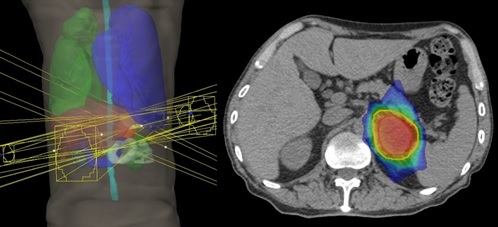

膵がん

切除可能な場合、手術が標準療法です。手術での取り残しを防ぐため、手術前に薬物療法を併用した放射線治療を行うことがあります。照射線量は40~50Gy、照射期間は3~6週間です。

高齢であったり心臓や肺の機能が悪くて手術ができない場合、あるいは手術で取り切れないと判断される場合は根治を目指した放射線治療を行うことがあります。照射線量は48-66Gy、照射期間は3~7週間です。

手術で取り残す可能性が高い箇所を中心にIMRTで照射。

胃や小腸、腎臓など周囲の臓器を避けて照射している。